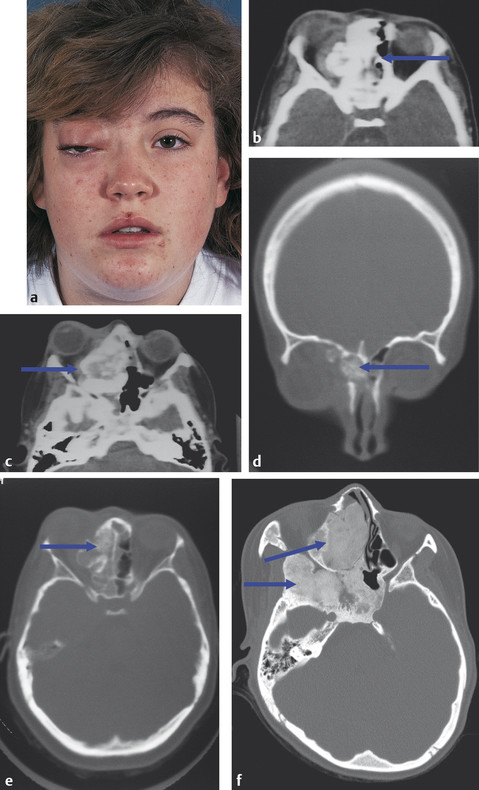

Enophthalmos may be subtle, presenting as a pseudoptosis or as a cosmetic asymmetry from the development of an upper lid sulcus. The causes are numerous and include the following:

Silent sinus syndrome (Fig. 18‑6a–d).

Metastatic carcinoma (Fig. 18‑6e–f).

Parry–Romberg’s syndrome (Fig. 18‑6g,h; Fig. 17.48b–d).